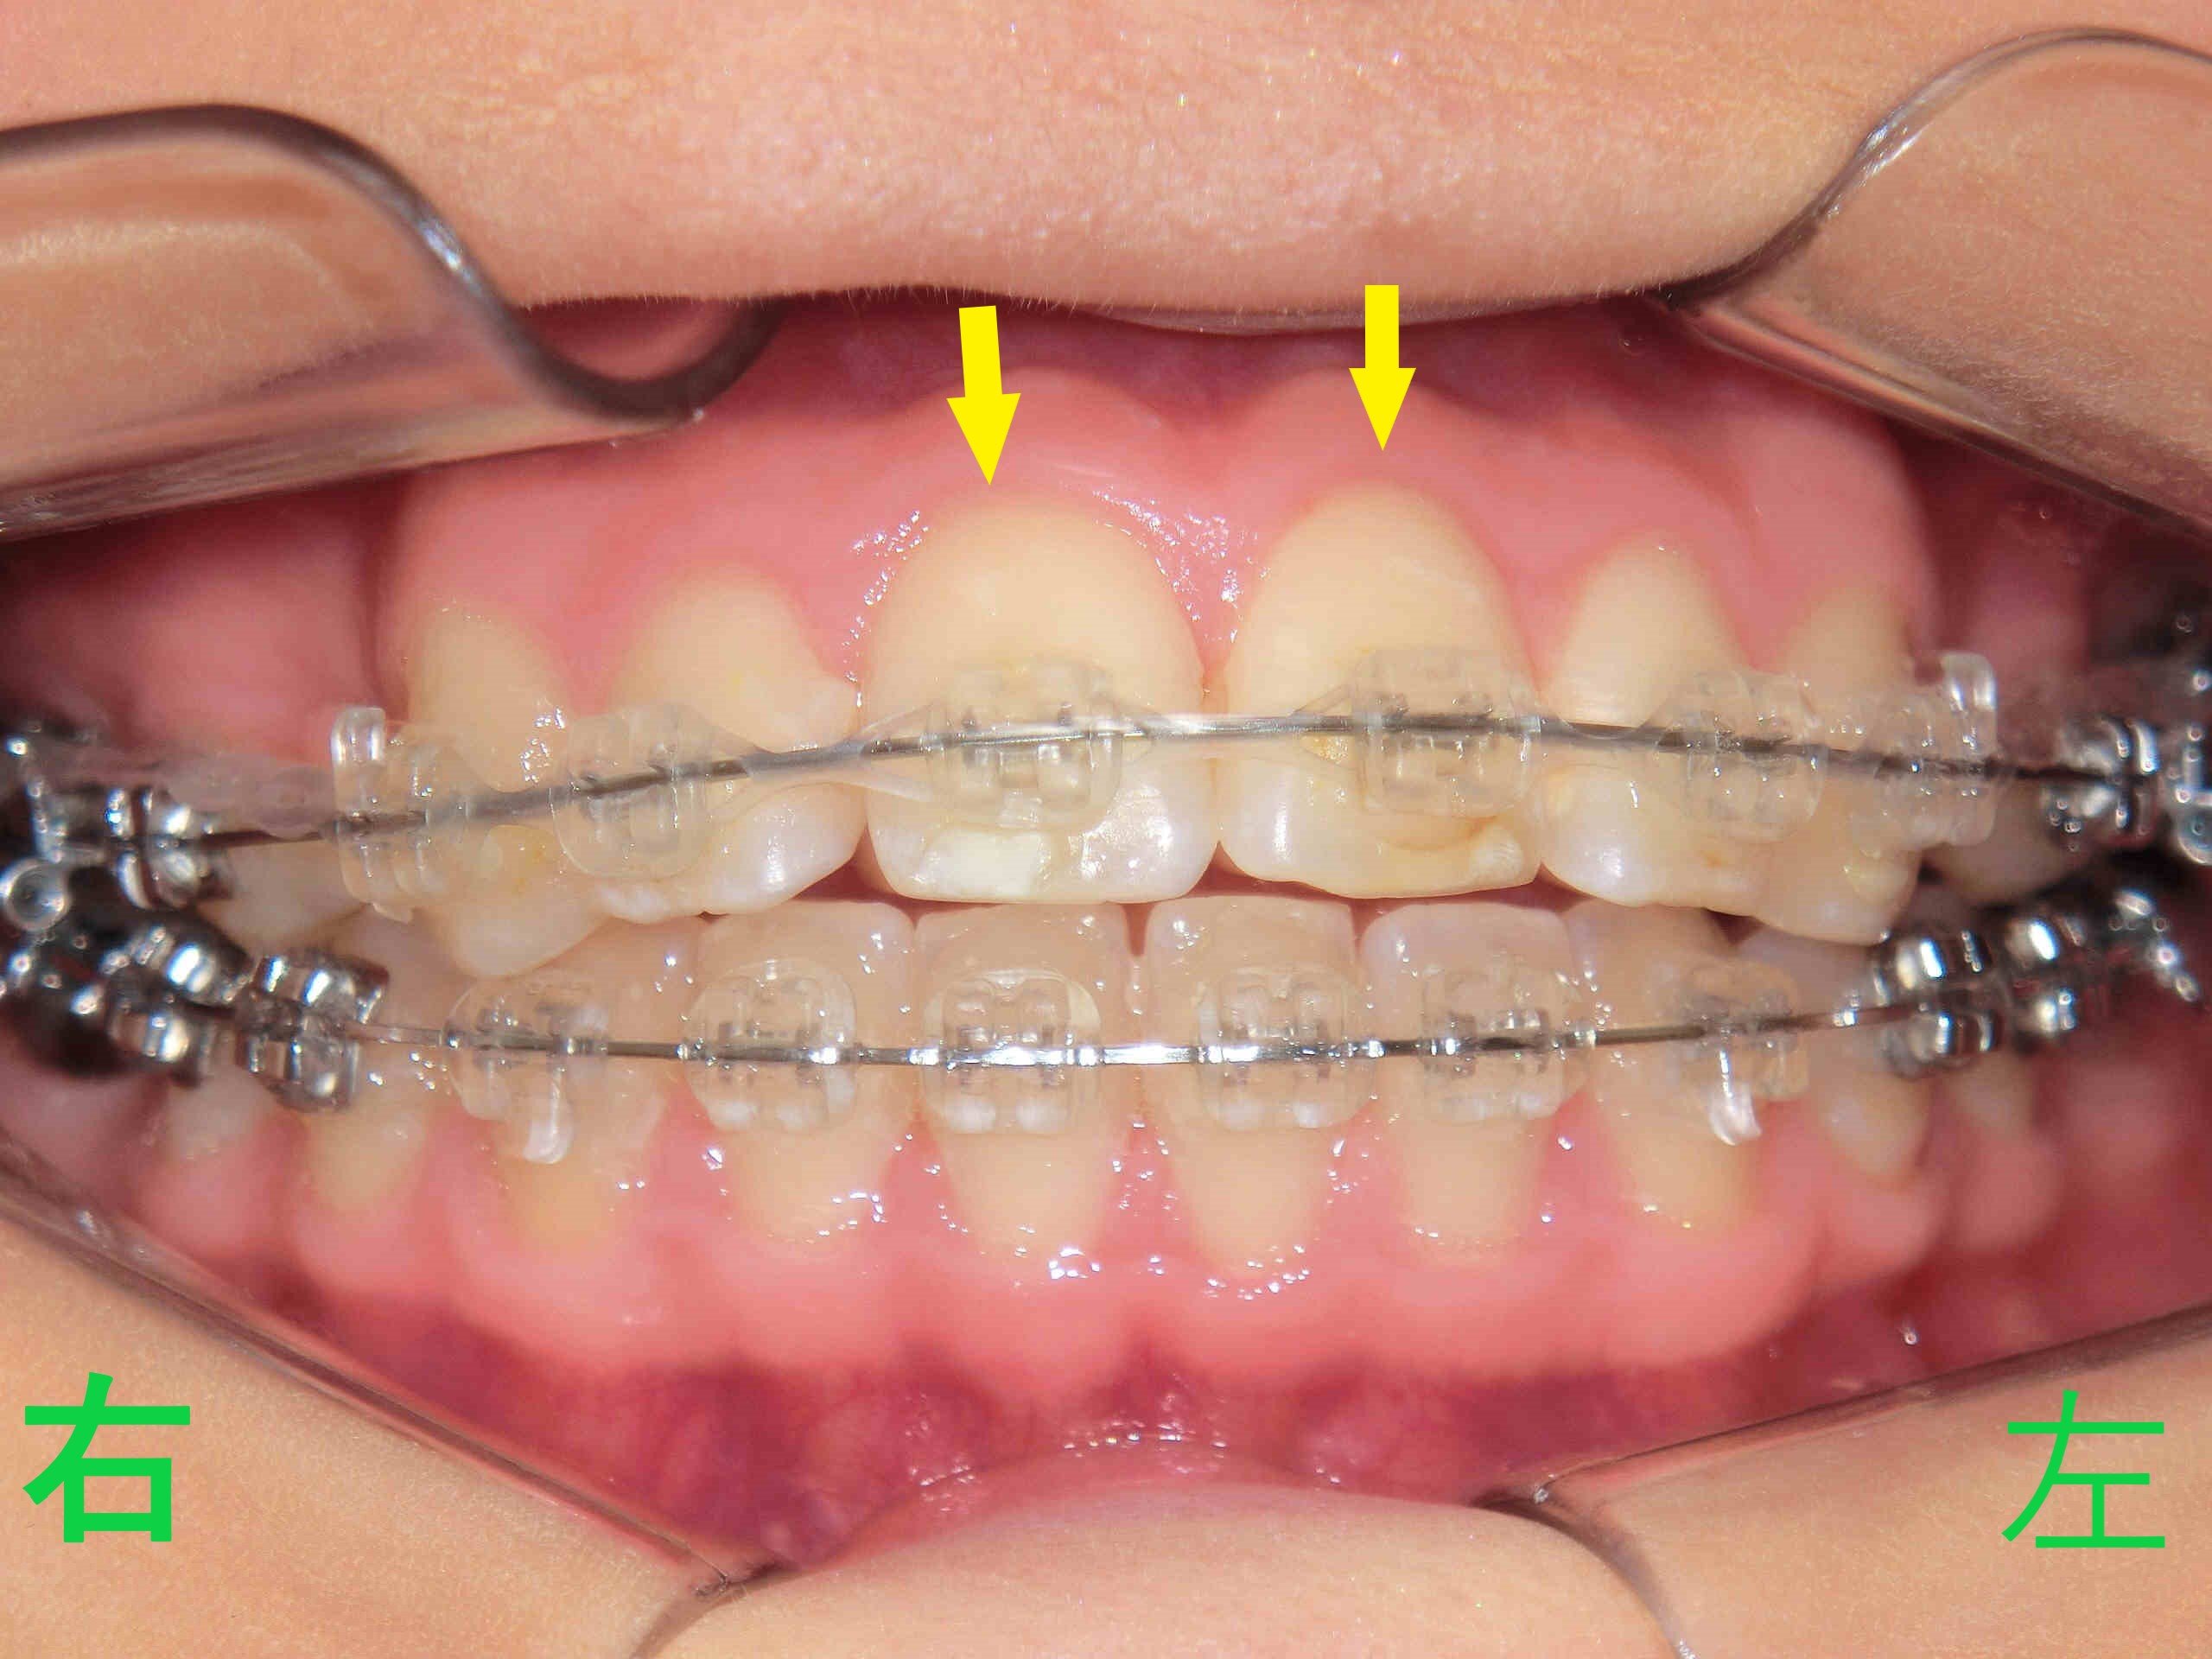

矯正開始から8か月後の口腔内写真では、上顎前歯(黄色矢印)の突出感が軽減され、下顎前歯との隙間が狭くなっているのが確認できます。

矯正開始から13か月後の写真では、上顎前歯の前突感がさらに軽減されているのが明瞭です(黄色矢印)。また、同時期の上顎歯列の写真(下から見上げたもの)では、抜歯した第一小臼歯のスペースがほぼ閉鎖されている様子が確認できます(青色矢印)。